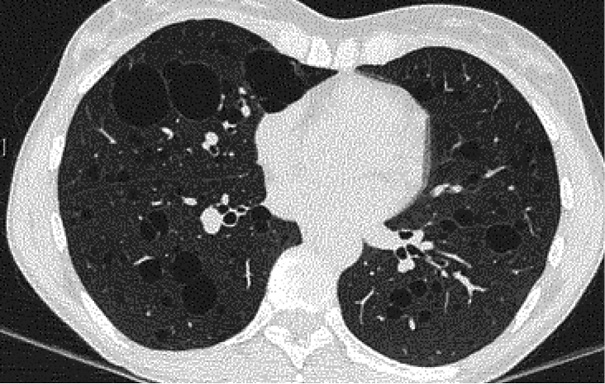

Given the recurrence of spontaneous pneumothoraces in a young individual without the traditional risk factors, high-resolution computed tomography (HRCT) of the chest was performed. HRCT demonstrated numerous bilateral, thin-walled cystic lesions ranging from 5 mm to 2 cm, with an upper-lobe predominance and several cysts abutting the pleural surface, consistent with the likely sites of rupture. No interstitial infiltrates, parenchymal nodules, or mediastinal lymphadenopathy were identified (Figure 2).

In the published literature on γ-HCD, lung manifestations include parenchymal infiltrates or secondary complications (for example, pulmonary hypertension responding to lenalidomide, or iatrogenic immunodeficiency-associated lymphoproliferative disease after methotrexate), but we were unable to identify prior reports in which diffuse cystic lung disease with recurrent pneumothorax was the sentinel presentation of γ-HCD [7,17]. This contrast is notable because cystic patterns are well documented in pulmonary LCDD, where thin-walled cysts (often with nodules) are typical and may progress to respiratory failure or necessitate transplantation. Our patient’s imaging therefore aligns radiographically with LCDD yet immunochemically fulfills criteria for γ-HCD, thus expanding the recognized pulmonary spectrum of heavy-chain dyscrasias [8,9,18–20].